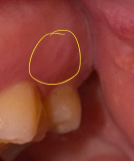

근데 해당 자리에 구내염 모양이 남아있어요. 15일이 되었는데 3mm정도의 작은 도넛 모양입니다.

잇몸에 생긴 구내염 자리가 15일이 지났음에도 도넛 모양으로 남아 있다면, 이는 흔히 흉 조직이나 잇몸 표면의 재생 과정 중에 나타날 수 있는 흔적일 수 있습니다. 상처가 아물면서 일시적으로 흉처럼 보일 수 있습니다.

이런 잔흔은 몇 주에서 몇 달에 걸쳐 점차 사라지는 경우가 많으니 너무 걱정하지 않아도 괜찮습니다.